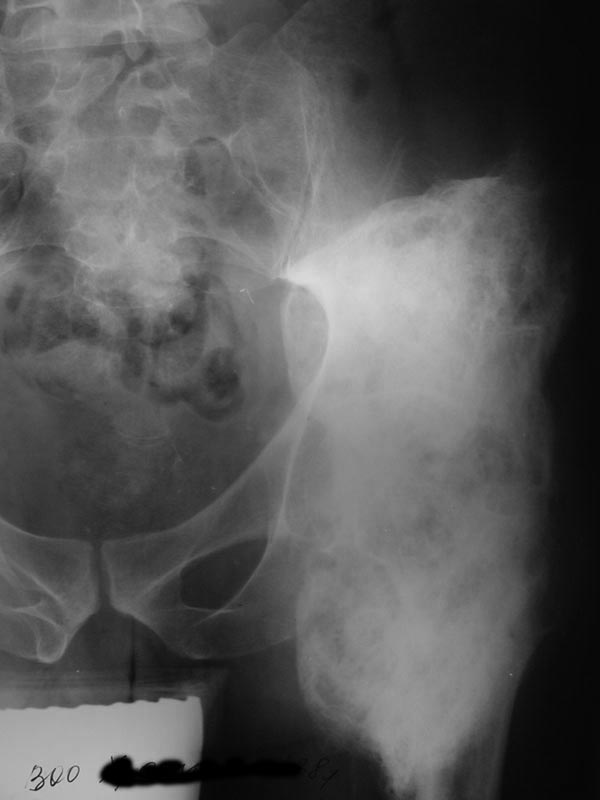

Мужчина 38 лет, Х.В.Н., диагноз: Закрытый травматический компрессионно-оскольчатый перелом L1 позвонка, вывих Тh 12, ушиб, сдавление спинного мозга, нижняя параплегия, нарушение функции тазовых органов. Операция 01.07.03: ламинэктомия Th 12-L1, задний спондилодез проволокой с протакрилом. 06.11.03 -- удаление протакрила, ламинэктомия Th 12-L1, декомпрессия спинного мозга, менингомиелолиз. У больного, как проявление нейродистрофического синдрома, сформировались грубые оссификаты вокруг обоих тазобедренных суставов с резким ограничением движений. 14.01.04 – операция иссечения переднебоковых оссификатов правого тазобедренного сустава. На операции достигнуто сгибание около 85 град. В послеоперационном периоде потеря коррекции значительна (более 50%). На сегодняшний день: Больной лежит, движения в тазобедренных суставах отсутствуют. По передней поверхности обоих суставов пальпируются плотные опухолевидные образования 6 х 8 см. На R-граммах: обширные оссификаты по передней и боковой поверхности т/бедренных суставов (см. приложенные файлы). Планируется оперативное лечение: иссечение оссификатов. Больного необходимо посадить в кресло-каталку для дальнейшей реабилитации. У кого есть предложения? Направление пациента на лечение согласовано с Министерством здравоохранения Хабаровского края, финансирование обещано. Лечащий врач Е.В.Квитченко